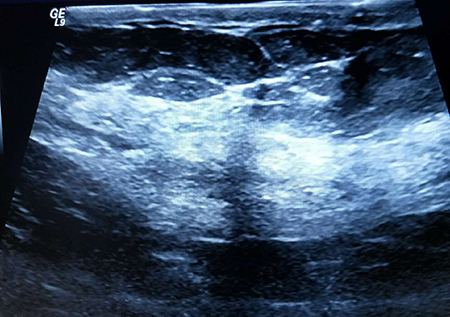

(图为乳腺超声图)